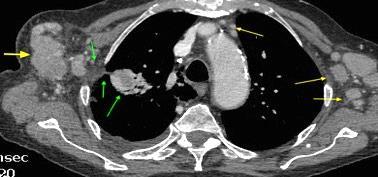

Masa axilar izquierda y derrame pleural derecho. Implantes pleurales, paraespinales . Ganglios en mamaria interna. Linfoma B difuso

Linfoma NH de cél. B. Invasión Transtorácica.

Afectación axilar

Conglomerado adenopático axila derecha. Linfoma de Hodgkin.

Santamarina MG et al. Multidetector CT for Evaluation of the Extrapleural Space. Radiographics 2017